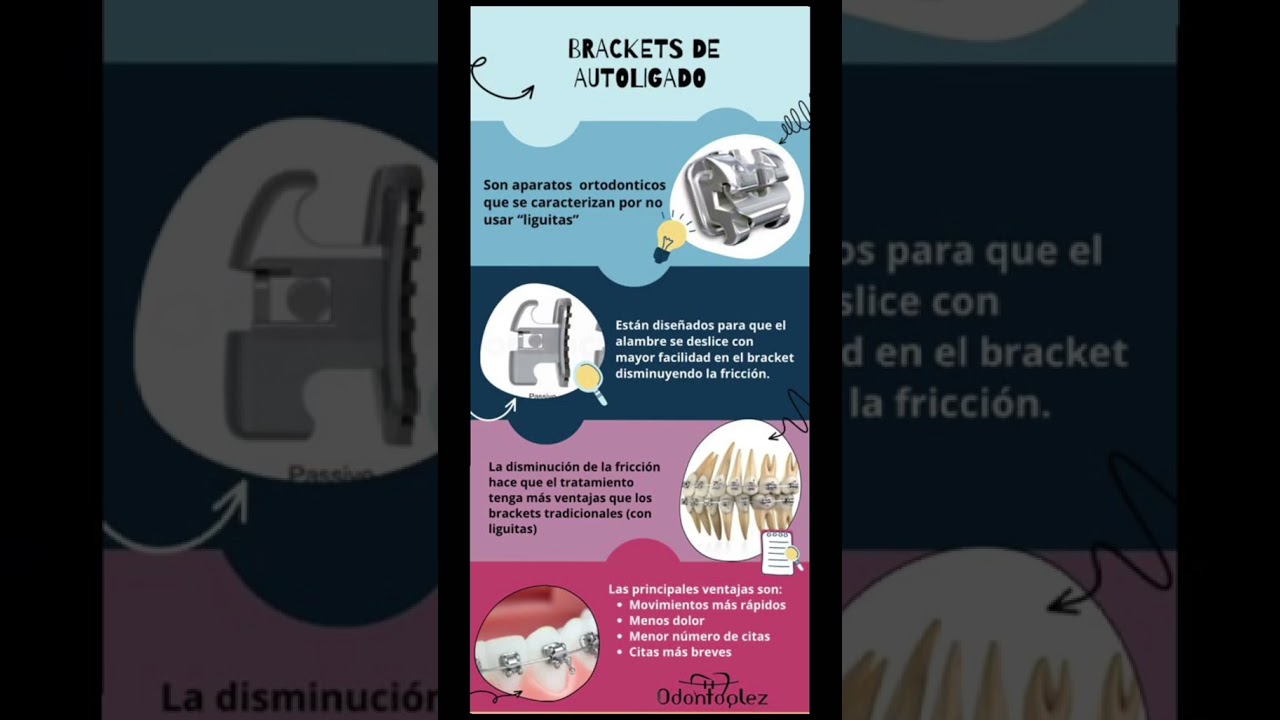

Ortodoncia autoligado

Desde $14,000 -

• Odontoglez • Brackets autoligado •

• Odontoglez • Ortodoncia autoligado •

• Odontoglez • Ortodoncia autoligado •